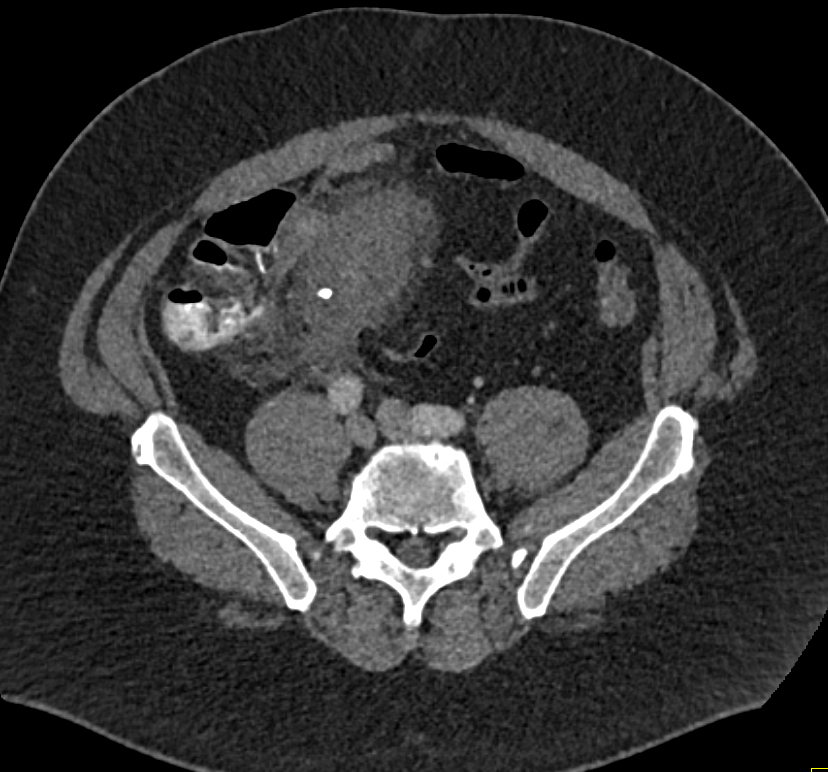

1) The CT finding in the abdominal wall is best known as?

herniation of small bowel

abscess

Sister Mary Joseph nodule

metastatic disease